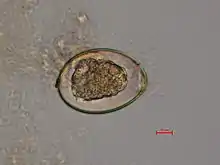

Diphyllobothrium latum – fertilized egg

The adult worm is composed of three fairly distinct morphological segments: the scolex (head), the neck, and the lower body. Each side of the scolex has a slit-like groove, which is a bothrium for attachment to the intestine. The scolex attaches to the neck, or proliferative region. From the neck grow many proglottid segments which contain the reproductive organs of the worm. D. latum is the longest tapeworm in humans, averaging ten meters long. Unlike many other tapeworms, Diphyllobothrium eggs are typically unembryonated when passed in human feces.[4]

Because humans do not generally eat undercooked minnows and similar small freshwater fish, these do not represent an important source of infection. Nevertheless, these small second intermediate hosts can be eaten by larger predator species, for example trout, perch, walleye, and pike. In this case, the sparganum can migrate to the musculature of the larger predator fish and mammals can acquire the disease by eating these later intermediate infected host fish raw or undercooked. After ingestion of the infected fish, the plerocercoids develop into immature adults and then into mature adult tapeworms which will reside in the small intestine. The adults attach to the intestinal mucosa by means of the two bilateral grooves (bothria) of their scolices. The adults can reach more than 10 m (up to 30 ft) in length in some species such as D. latum, with more than 3,000 proglottids. One or several of the tape-like proglottid segments (hence the name tapeworm) regularly detach from the main body of the worm and release immature eggs in freshwater to start the cycle over again. Immature eggs are discharged from the proglottids (up to 1,000,000 eggs per day per worm) and are passed in the feces. The incubation period in humans, after which eggs begin to appear in the feces is typically 4–6 weeks, but can vary from as short as 2 weeks to as long as 2 years.[7]